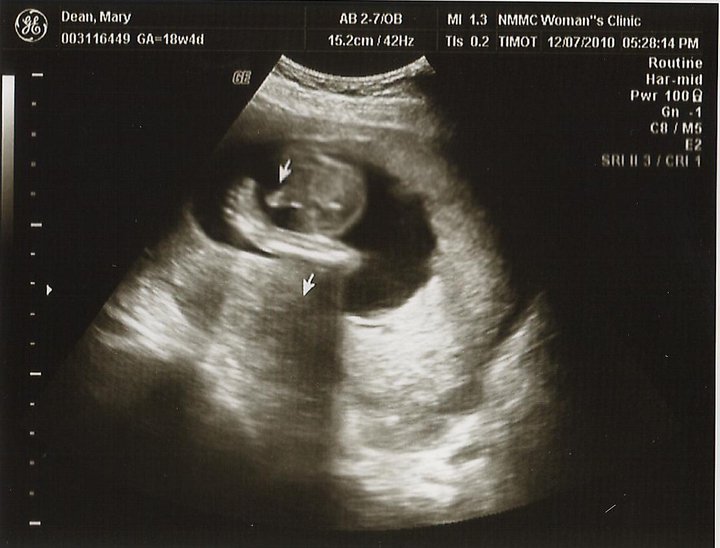

I've been growing up a storm, as you can see in the pictures below! Momma went to the doctor Monday and I weighed in at 1 lb. 14 oz. I'm in the 56th percentile for my gestational age (GA). Right now I'm still working on growing taller so one day I can be taller than Daddy, but I'm also putting on some fat to keep me warm once I arrive. I wonder how big I'll be.

|

| And at 18 weeks GA. Look how much I've grown! |